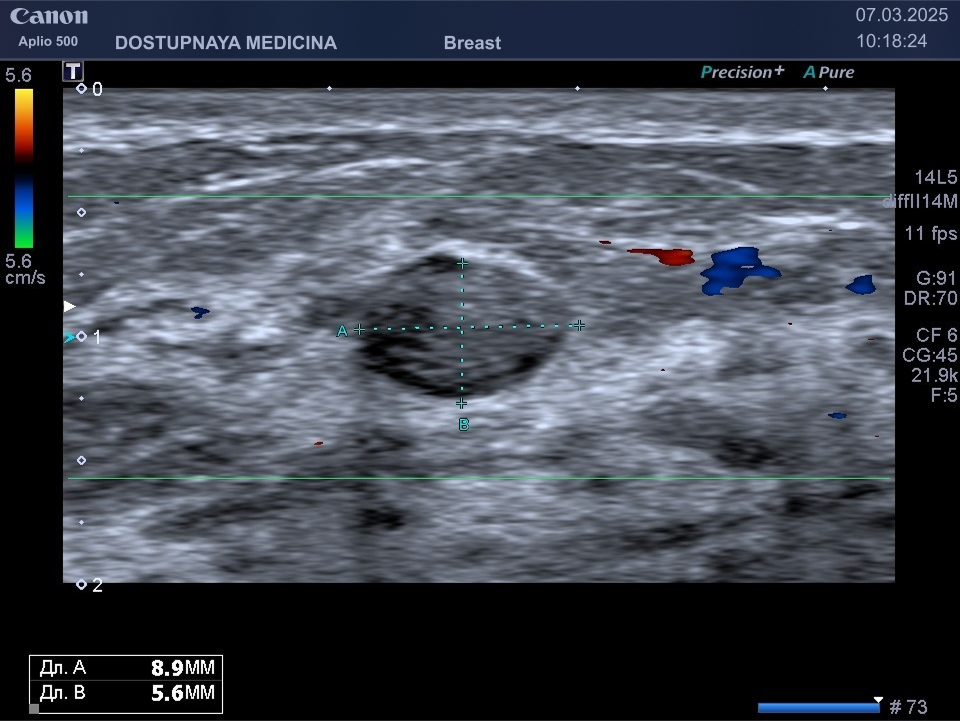

Фиброаденома молочной железы – это достаточно часто выявляемая опухоль во время ультразвукового исследования, состоящая из железистой ткани с довольно выраженной соединительнотканной капсулой.

Следует проводить дифференциальную диагностику фиброаденомы с раком молочной железы, с кистой и с цистаденопапилломой. Поэтому важно повторить ультразвуковое исследование через 3 месяца, а затем при отсутствии тенденции к росту опухоли необходим УЗИ контроль через 6 месяцев.

Киста может быть заполнена жидким или густым секретом. Киста с жидким секретом на УЗИ выглядит как анэхогенное (чёрное) образование округлой или овальной формы, киста с густым секретом на УЗИ выглядит как гипоэхогенное (серое) образование.

Встречаются атипичные кисты, содержащие перегородки и имеющие неправильную форму. Такие кисты имеют большую степень онкологической настороженности и относятся к категории BI-RADS3, соответственно требуют более тщательного наблюдения.